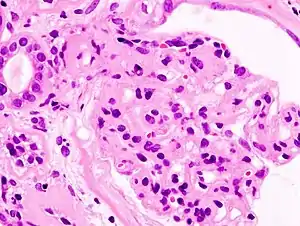

_HE.jpg.webp)

A kidney biopsy may also be used as a more specific and invasive test method. A study of a sample's anatomical pathology may then allow the identification of the type of glomerulonephritis involved.[35] However, this procedure is usually reserved for adults as the majority of children experience minimal change disease that has a remission rate of 95% with corticosteroids.[37] A biopsy is usually only indicated for children that are corticosteroid resistant as the majority have focal and segmental glomeruloesclerosis.[37]